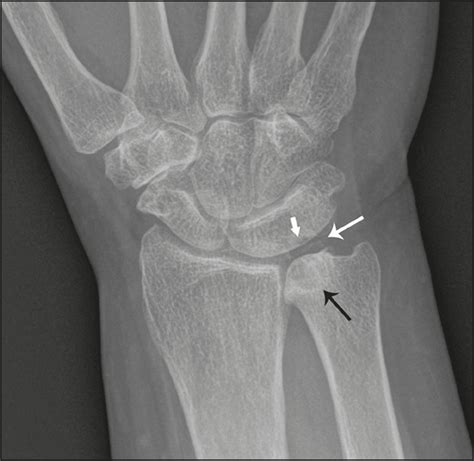

At its core, Ulnar Impaction Syndrome is a degenerative condition characterized by the mechanical abutment of the distal ulna—the bone on the pinky side of your forearm—against the bones in the wrist (specifically the lunate and triquetrum) and the triangular fibrocartilage complex (TFCC). In a healthy wrist, the radius and ulna work in harmony to support the carpal bones. However, if the ulna is relatively longer than the radius, a condition called “ulna positive variance,” it creates a crowded space that leads to repetitive grinding, cartilage wear, and ligament tears.

Imaging is equally vital. Standard X-rays, particularly those taken in a neutral position, help clinicians measure the ulnar variance. In more complex cases, an MRI is ordered to evaluate the extent of TFCC damage, cartilage wear on the lunate, or subchondral bone edema, which is the "bruising" of the bone caused by persistent impaction.